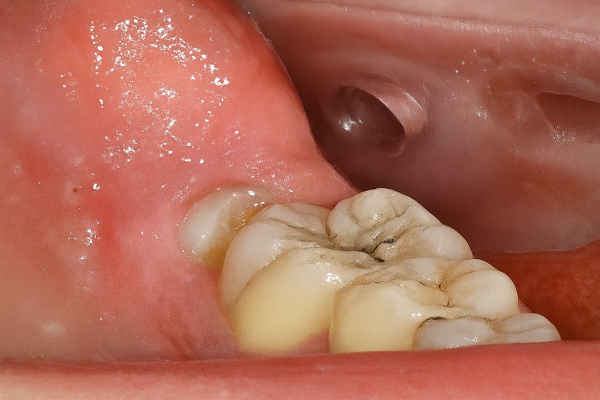

Retención de segundos molares mandibulares: evaluación mediante CBCT y consideraciones terapéuticas ante un caso clínico